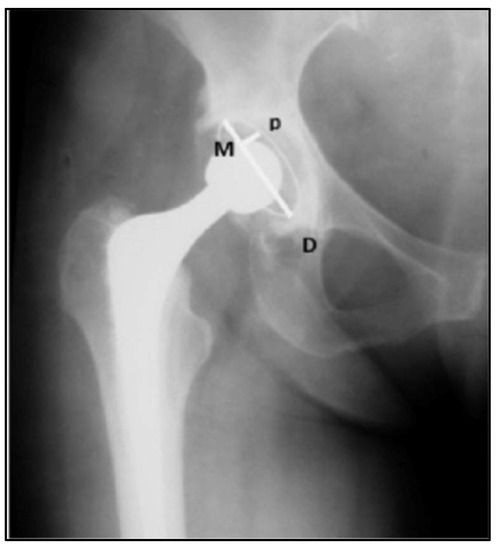

2.3. Analysis of Radiographic Parameters: Positioning and Inclinations of the Acetabular Component

| Acetabular placement (degrees) | 44.3 ± 5.9 | 44.4 ± 6.3 | 0.083 |